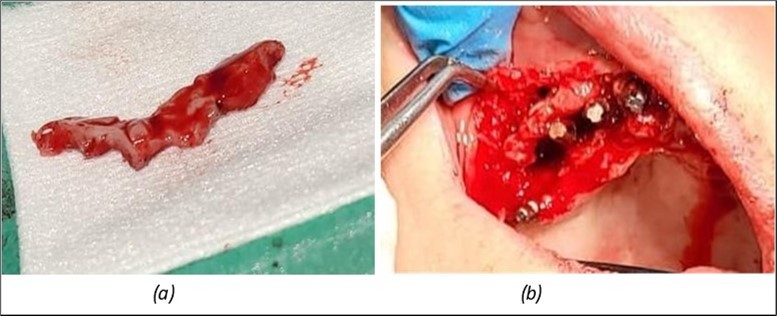

In the upper anterior region, after extractions and regularization, marginal gingival connective tissue located palatine is harvested for use in augmenting the anterior area. This tissue is de-epithelized with a scalpel and kept in saline solution until used (Figure 4, Figure 5). The implants used are BCS corticobasal implants in areas with significant bone loss, and TPG compression implants, both from Dr. Ihde Dental AG, for post-extraction areas and regions with a large amount of trabecular bone but of poor quality (D3-D4). Both types of implants have a polished surface to reduce bacterial adhesion, and they feature a 2mm prosthetic collar that can be bent to parallelize the prosthetic part of the implant according to prosthetic requirements (Figure 3). The only exception to this parallelization through bending is the TPG implant in the maxillary-sphenoid fusion area (quadrant 2), were, due to lower torque, a prefabricated parallelization sleeve with a 25° angle was preferred. This sleeve was cemented before the impression was taken (Figure 3).

Considerations related to connective tissue grafting in post-extraction and post-implant defects – it is a technique that can be performed either by harvesting connective tissue from the tuberosity area, the palate, or the marginal palatal area, if the quantity is sufficient 11. It is done simultaneously with the rest of the bone regularization procedure; in this case, removal of the palatal gingival area was necessary anyway for easier cleaning and access to the frontal implants. On this occasion, after de-epithelialization, the tissue is used to restore the shape of the frontal gingival area after implant insertion (Figure 4, Figure 5).

Figure 4.Repair of the frontal area with connective tissue harvested from the marginal palatal area after extraction and crest regularization: (a) mucosal tissue piece harvested from the frontal palatal area before preparation; (b) prepared connective tissue piece placed between the frontal implants under the mobile mucosa.